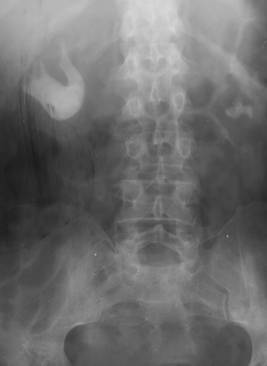

Fig. 58 – Ectopie bilaterala, lombara dreapta si presacrata stanga (vezica cu amprenta uterina pe conturul superior)